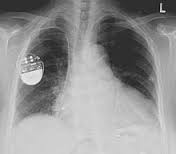

Les seuls problèmes que peuvent rencontrer le patients est une allergie aux produits utilisés pour l'examen ou des effets secondaires liés aux DMI (Dispositif Médical Implanté) qu'il possède.

Les DMI sont tels que des:

-pièces métalliques

-appareils électroniques (simulateurs cardiaque,neurosimulateurs)

-valves cardiaques

-dispositifs auditifs

Ceux-ci peuvent amnener à des lésions tissulaires liées à la rotation de l'objet ou un dysfonctionnement de l'appareil.